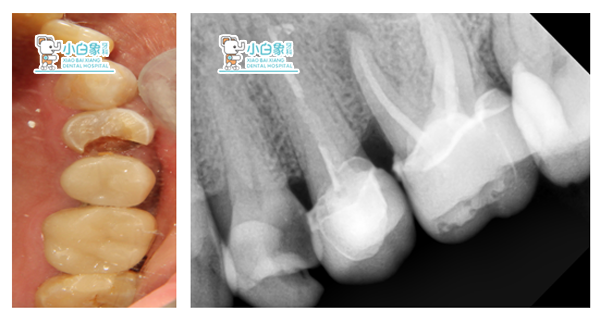

检查:24远中邻合面龋坏达牙本质深层,叩诊(土),温度试验迟钝,牙龈无红肿。25 26全瓷冠修复,边缘密合,牙龈无红肿。全口牙龈部分退缩,牙龈无红肿。

X线:24低密度影近髓角

25 26根充良好

治疗:24必兰麻醉下上橡皮障,去腐质,开髓揭顶,预备根管两根,根长21mm,次氯酸钠冲洗,隔湿干燥 ,试尖,根充,磷酸锌垫底,3MZ250充填,调合。